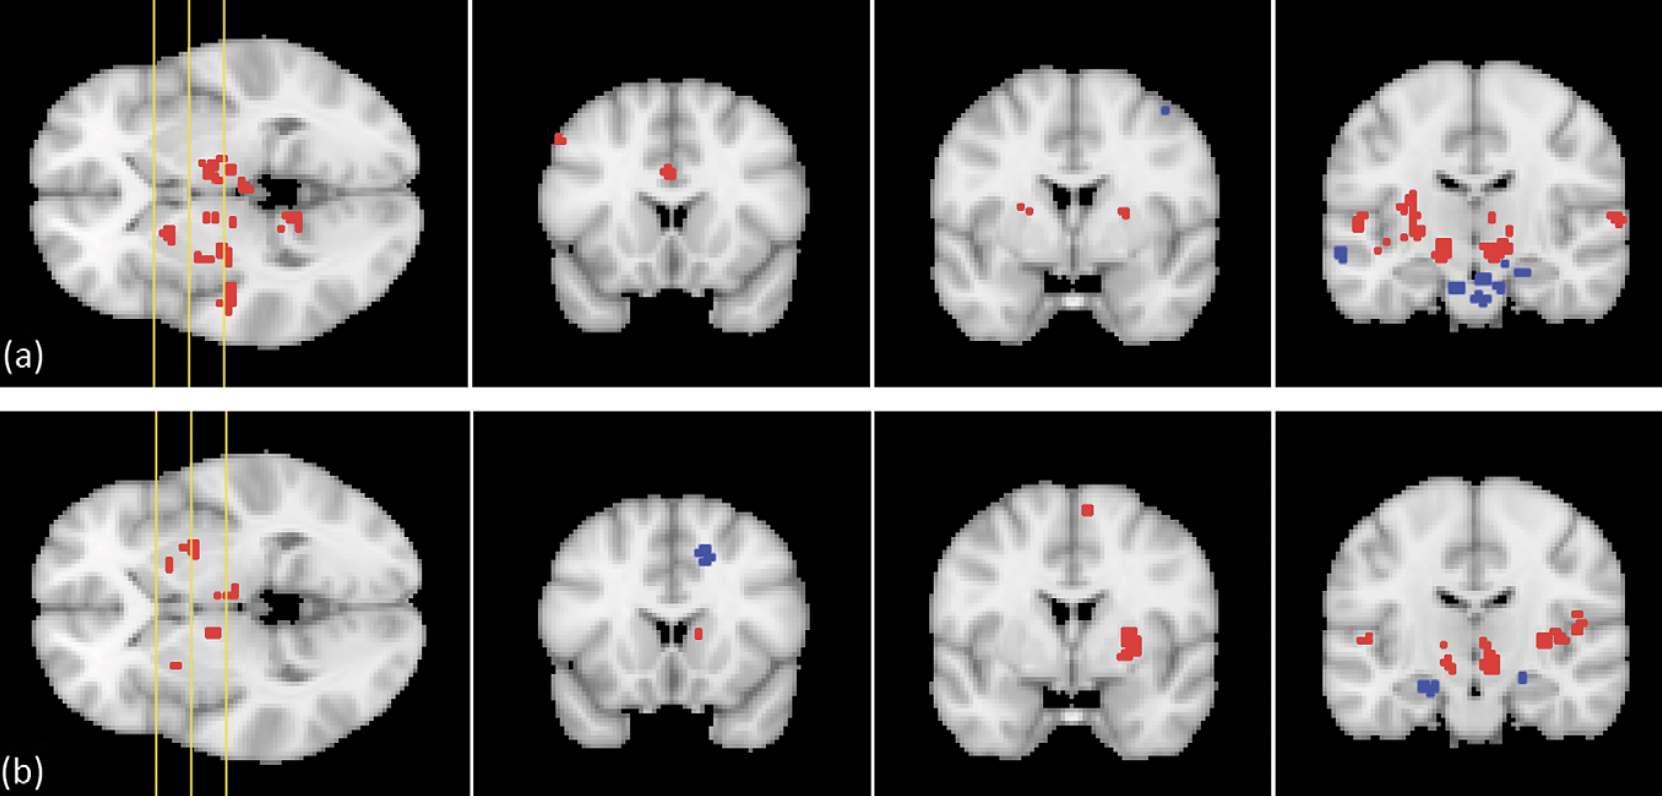

Significant functional connectivity clusters for (a) the right and (b) the left atlas-based STN ROIs, shown on three coronal slices of the MNI152 template. The yellow lines on the axial image on the left-hand side show the position of the coronal slices. Red clusters exhibit positive regression coefficients, while blue clusters yield negative coefficients

Deep brain stimulation (DBS) for Parkinson's disease often alleviates the motor symptoms, but causes cognitive and emotional side effects in a substantial number of cases. Identification of the motor part of the subthalamic nucleus (STN) as part of the presurgical workup could minimize these adverse effects. In this study, we assessed the STN�s connectivity to motor, associative, and limbic brain areas, based on structural and functional connectivity analysis of volunteer data. For the structural connectivity, we used streamline counts derived from HARDI fiber tracking. The resulting tracks supported the existence of the so-called hyperdirect pathway in humans. Furthermore, we determined the connectivity of each STN voxel with the motor cortical areas. Functional connectivity was calculated based on functional MRI, as the correlation of the signal within a given brain voxel with the signal in the STN. Also, the signal per STN voxel was explained in terms of the correlation with motor or limbic brain seed ROI areas. Both right and left STN ROIs appeared to be structurally and functionally connected to brain areas that are part of the motor, associative, and limbic circuit. Furthermore, this study enabled us to assess the level of segregation of the STN motor part, which is relevant for the planning of STN DBS procedures.